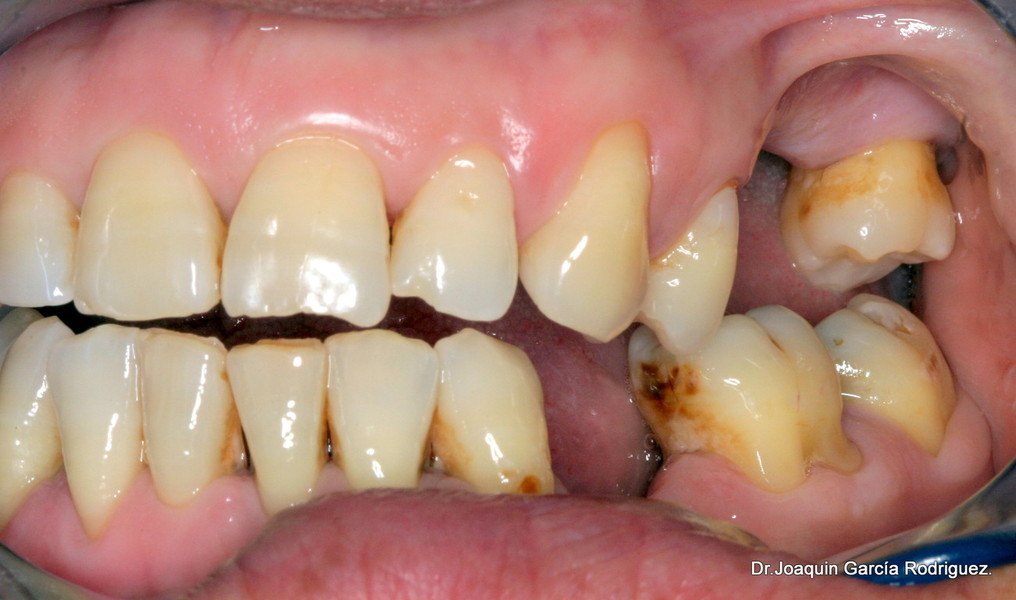

Paciente joven de 40 años, mujer, con altas exigencias estéticas, afectada de enfermedad periodontal avanzada del adulto y trauma de oclusión en el sector anterior que afecta a las piezas 11 y 21, incisivos centrales, tiene sobremordida anterior y ausencia de disclusión canína.

Lo fundamental es establecer un meticuloso diagnostico, donde a través del análisis estético de la sonrisa, iniciar un plan de tratamiento de excelencia profesional que nos permita, en primer lugar eliminar la enfermedad periodontal, parar la reabsorción ósea, corregir el trauma anterior, regenerar los tejidos blandos y restablecer la función, con una prótesis estética.

En el análisis estético, analizaremos la forma de la cara, la nariz, el ángulo nasolabial, el tono de los labios, la forma de los dientes, el tamaño, la linea media, la encía si es supragingival o infragingial, el biotipo de la misma si es fino o grueso.

En este caso nos decidimos por las coronas de circonio, ya que si se produce una recesión gingival, jamás se evidenciará el metal.